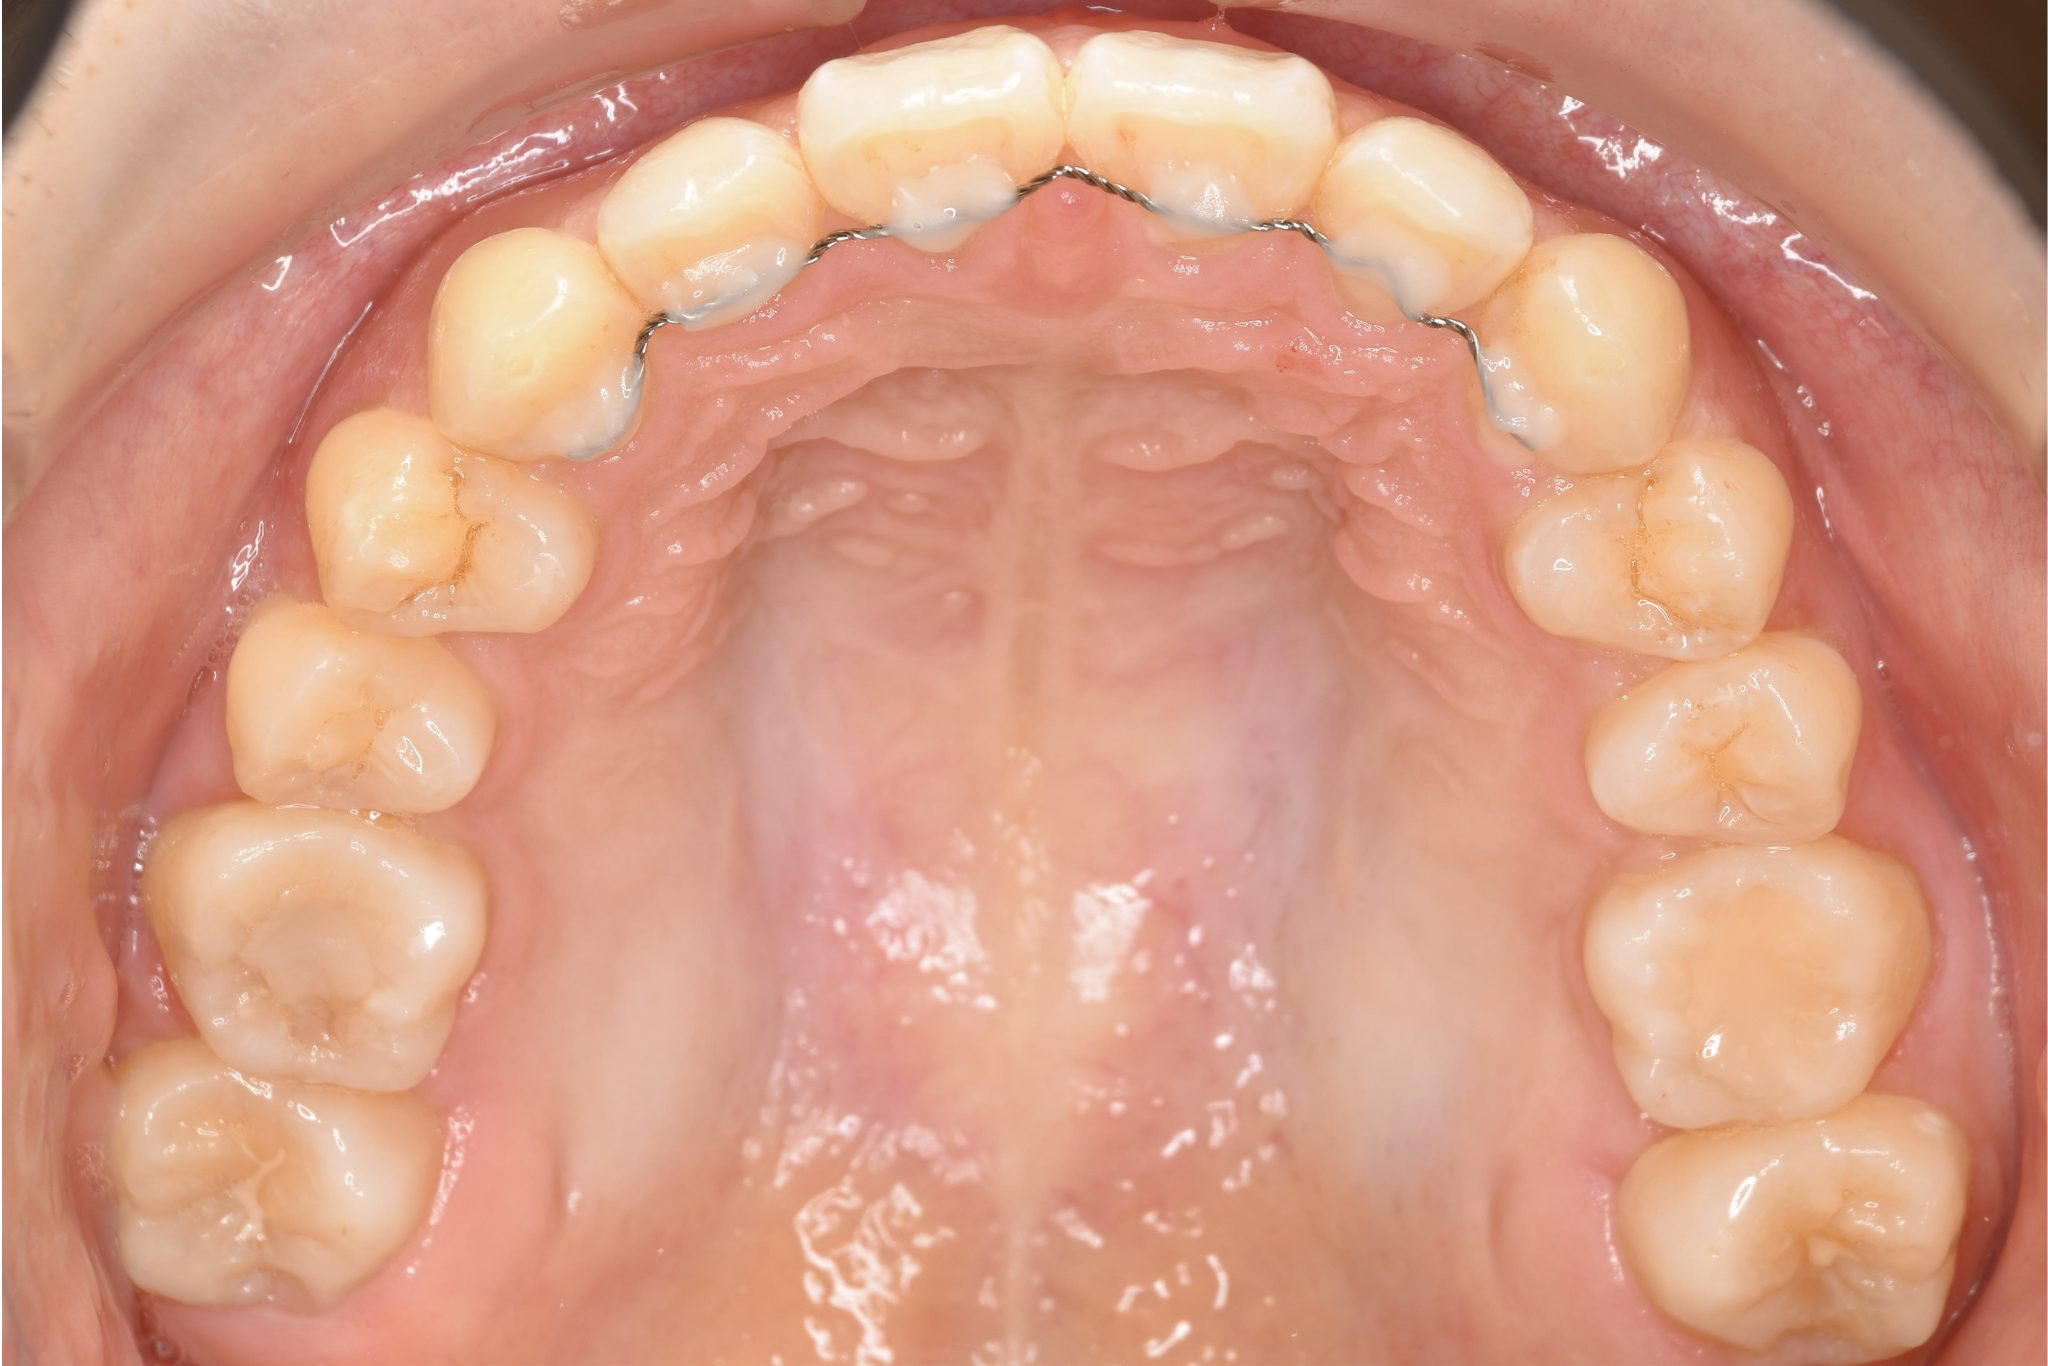

ワイヤー矯正治療|症例_349 Case

ワイヤー矯正治療|症例_349

主訴 下の前歯が見えない|歯がガタガタ

施術内容 MSEと下顎リンガルアーチを用いて上下顎骨を拡大した。

その後マルチブラケット装置を用いて非抜歯で歯牙を配列し、良好な咬合を獲得した。

治癒期間 3年7か月間